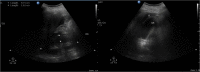

Dengue fever is a mosquito-borne arthropod-borne viral (arboviral) tropical disease in humans affecting 50-528 million people worldwide. The acute abdominal complications of dengue fever are acute appendicitis, acute pancreatitis, acute acalculous cholecystitis and non-specific peritonitis. Acute pancreatitis with new onset diabetes in dengue shock syndrome (DSS) is very rarely reported. We describe a case of 30-year-old man admitted in intensive care unit and was diagnosed with DSS with RT-PCR, NS1 antigen and dengue IgM antibody being positive. Abdominal ultrasound and computerized tomography confirmed acute pancreatitis. Patient required insulin after recovery. Diabetes mellitus caused by DSS is under-reported and lack of awareness may increase mortality and morbidity.